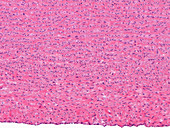

12360983 - Kidney, light micrograph

12360908 - Kidney glomeruli, light micrograph

12360952 - Convoluted tubules, light micrograph

13613443 - Human aorta, light micrograph